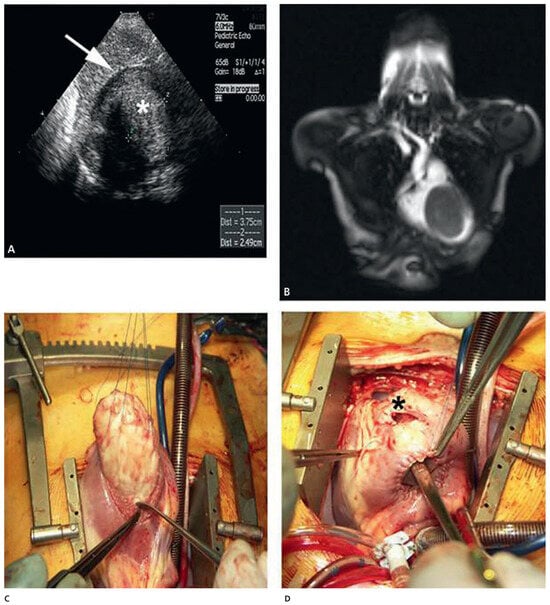

A patient with Morbus Behçet was admitted with severe symptomatic aortic regurgitation caused by aortitis that mimicked infective endocarditis. After aortic valve replacement and antibiotic treatment, regurgitation and systemic inflammation recurred....